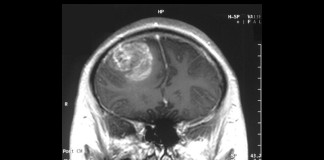

CAR-T Cell Therapy Achieves Near-Complete Tumor Regression in Brain Cancer After Five Days

Mar 14, 2024

Science